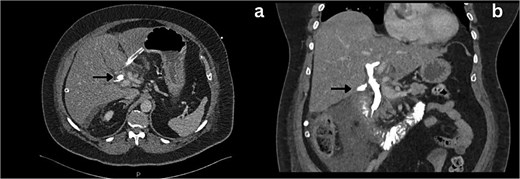

Following a brief clinical response to the initial conservative management for 24 hours, the patient started deteriorating and developed generalized peritonitis with worsening of inflammatory markers (C-reactive protein escalated to 438 mg/l). Consequently, she underwent an emergency diagnostic laparoscopy as the cause of peritonitis was not clear. Intraoperatively, it was observed that there was free bile in the peritoneal cavity, more so around the liver and the right paracolic gutter. There was also a bile collection behind the right colon and hepatic flexure of the colon, raising the possibility of a retroperitoneal source. The hepatic flexure of the colon was mobilized to assess the source of the leak. No obvious ongoing leak was noticed. As a precautionary measure, an Upper GI endoscopy was conducted intra-operatively to rule out any gastroduodenal perforation, as no obvious source of bile leak was seen from the biliary tree. This revealed the presence of bile in the stomach and confirmed normal anatomy up to the third part of the duodenum. The remaining intra-abdominal organs appeared unremarkable. Thorough peritoneal lavage was given, and 22 Fr abdominal drains were placed in the subhepatic, para-hepatic space, and pelvis, respectively, as the source of leak was not found. The following day, an endoscopic retrograde cholangiopancreatography (ERCP) was performed, which identified a small leak around the area of the cystic duct stump (Fig. 3). In response, a 5 cm-sized 7 Fr double pigtail stent was inserted into the CBD. A post-ERCP CT scan was performed to evaluate the contrast leak. The CT imaging revealed an extraluminal contrast leak originating from a defect in the posterior CBD (Fig. 4). Notably, the cystic duct stump remained intact and anterior, establishing the diagnosis of Spontaneous biliary leak from the CBD.

ERCP imaging reveals contrast leak in the cystic duct stump region.